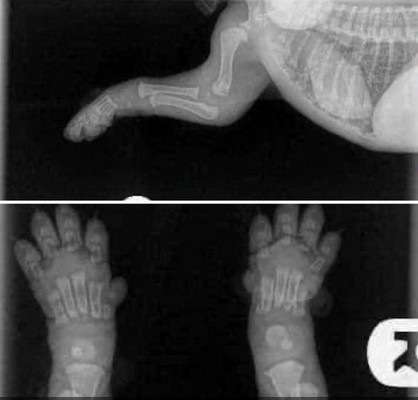

X-ray of newborn puppy | X-ray of a puppy in age 2 weeks | |

HEALTH: Since 1992 we have been doing x-rays of hip and elbow joints Together with Ala Cecrdlova, we were one of the first breeders who pushed for the introduction of the obligation of these health examinations for inclusion among the breeding conditions of retrievers in the Czech Republic. The second health aspect, which we consider very important, is the eye examination. Because we are convinced of itprinciple that the breed, which is most often used as a guide dog, must itself have completely healthy eyes. Our dogs therefore undergo a genetic test for Progressive Retinal Atrophy, Progressive Rod-Cone Degeneration (PRA-prcd). Another genetically tests which our dogs undergo: Centronuclear Myopathy (CNM) Cystinuria, Degenerative Myelopathy (DM) Exercise Induced Collapse (EIC) Hereditary Nasal Parakeratosis (HNPK) Tests of our dogs are sending for evaluation to the DDC DNA Diagnostic Center laboratory in Fairfield, Ohio, USA. Based on the results of these health tests, we then place our dogs in breedin. Also for mating of our females we choose dogs that have also passed genetic tests. Therefore we are able to guarantee future owners that a puppy from us will never get sick with any of the aforementioned genetic defects. We always inform all new owners of our puppies how important a correct and responsible approach to their development is in the first year of life. Because the skeleton and joints - his entire supporting structure - develop up to a year and a half, it is very important to maintain great patience during this period and refrain from overexerting yourself with movement. Proper nutrition is also very important during the development period. To give you a better idea - a puppy in the period up to 18 months will go through the same phase of development as a child up to 15 years old. I.e. for what a human child has 15 years = 180 months for his development, a dog puppy has has only 18 months = 10x less time for his development. That is why it´s very important to maintain a resting regime for a sufficiently long time, especially for larger and giant breeds of dogs. The Labrador, despite being classified as a medium breed, needs, due to its adult weight, the same considerations as large breeds. | ||